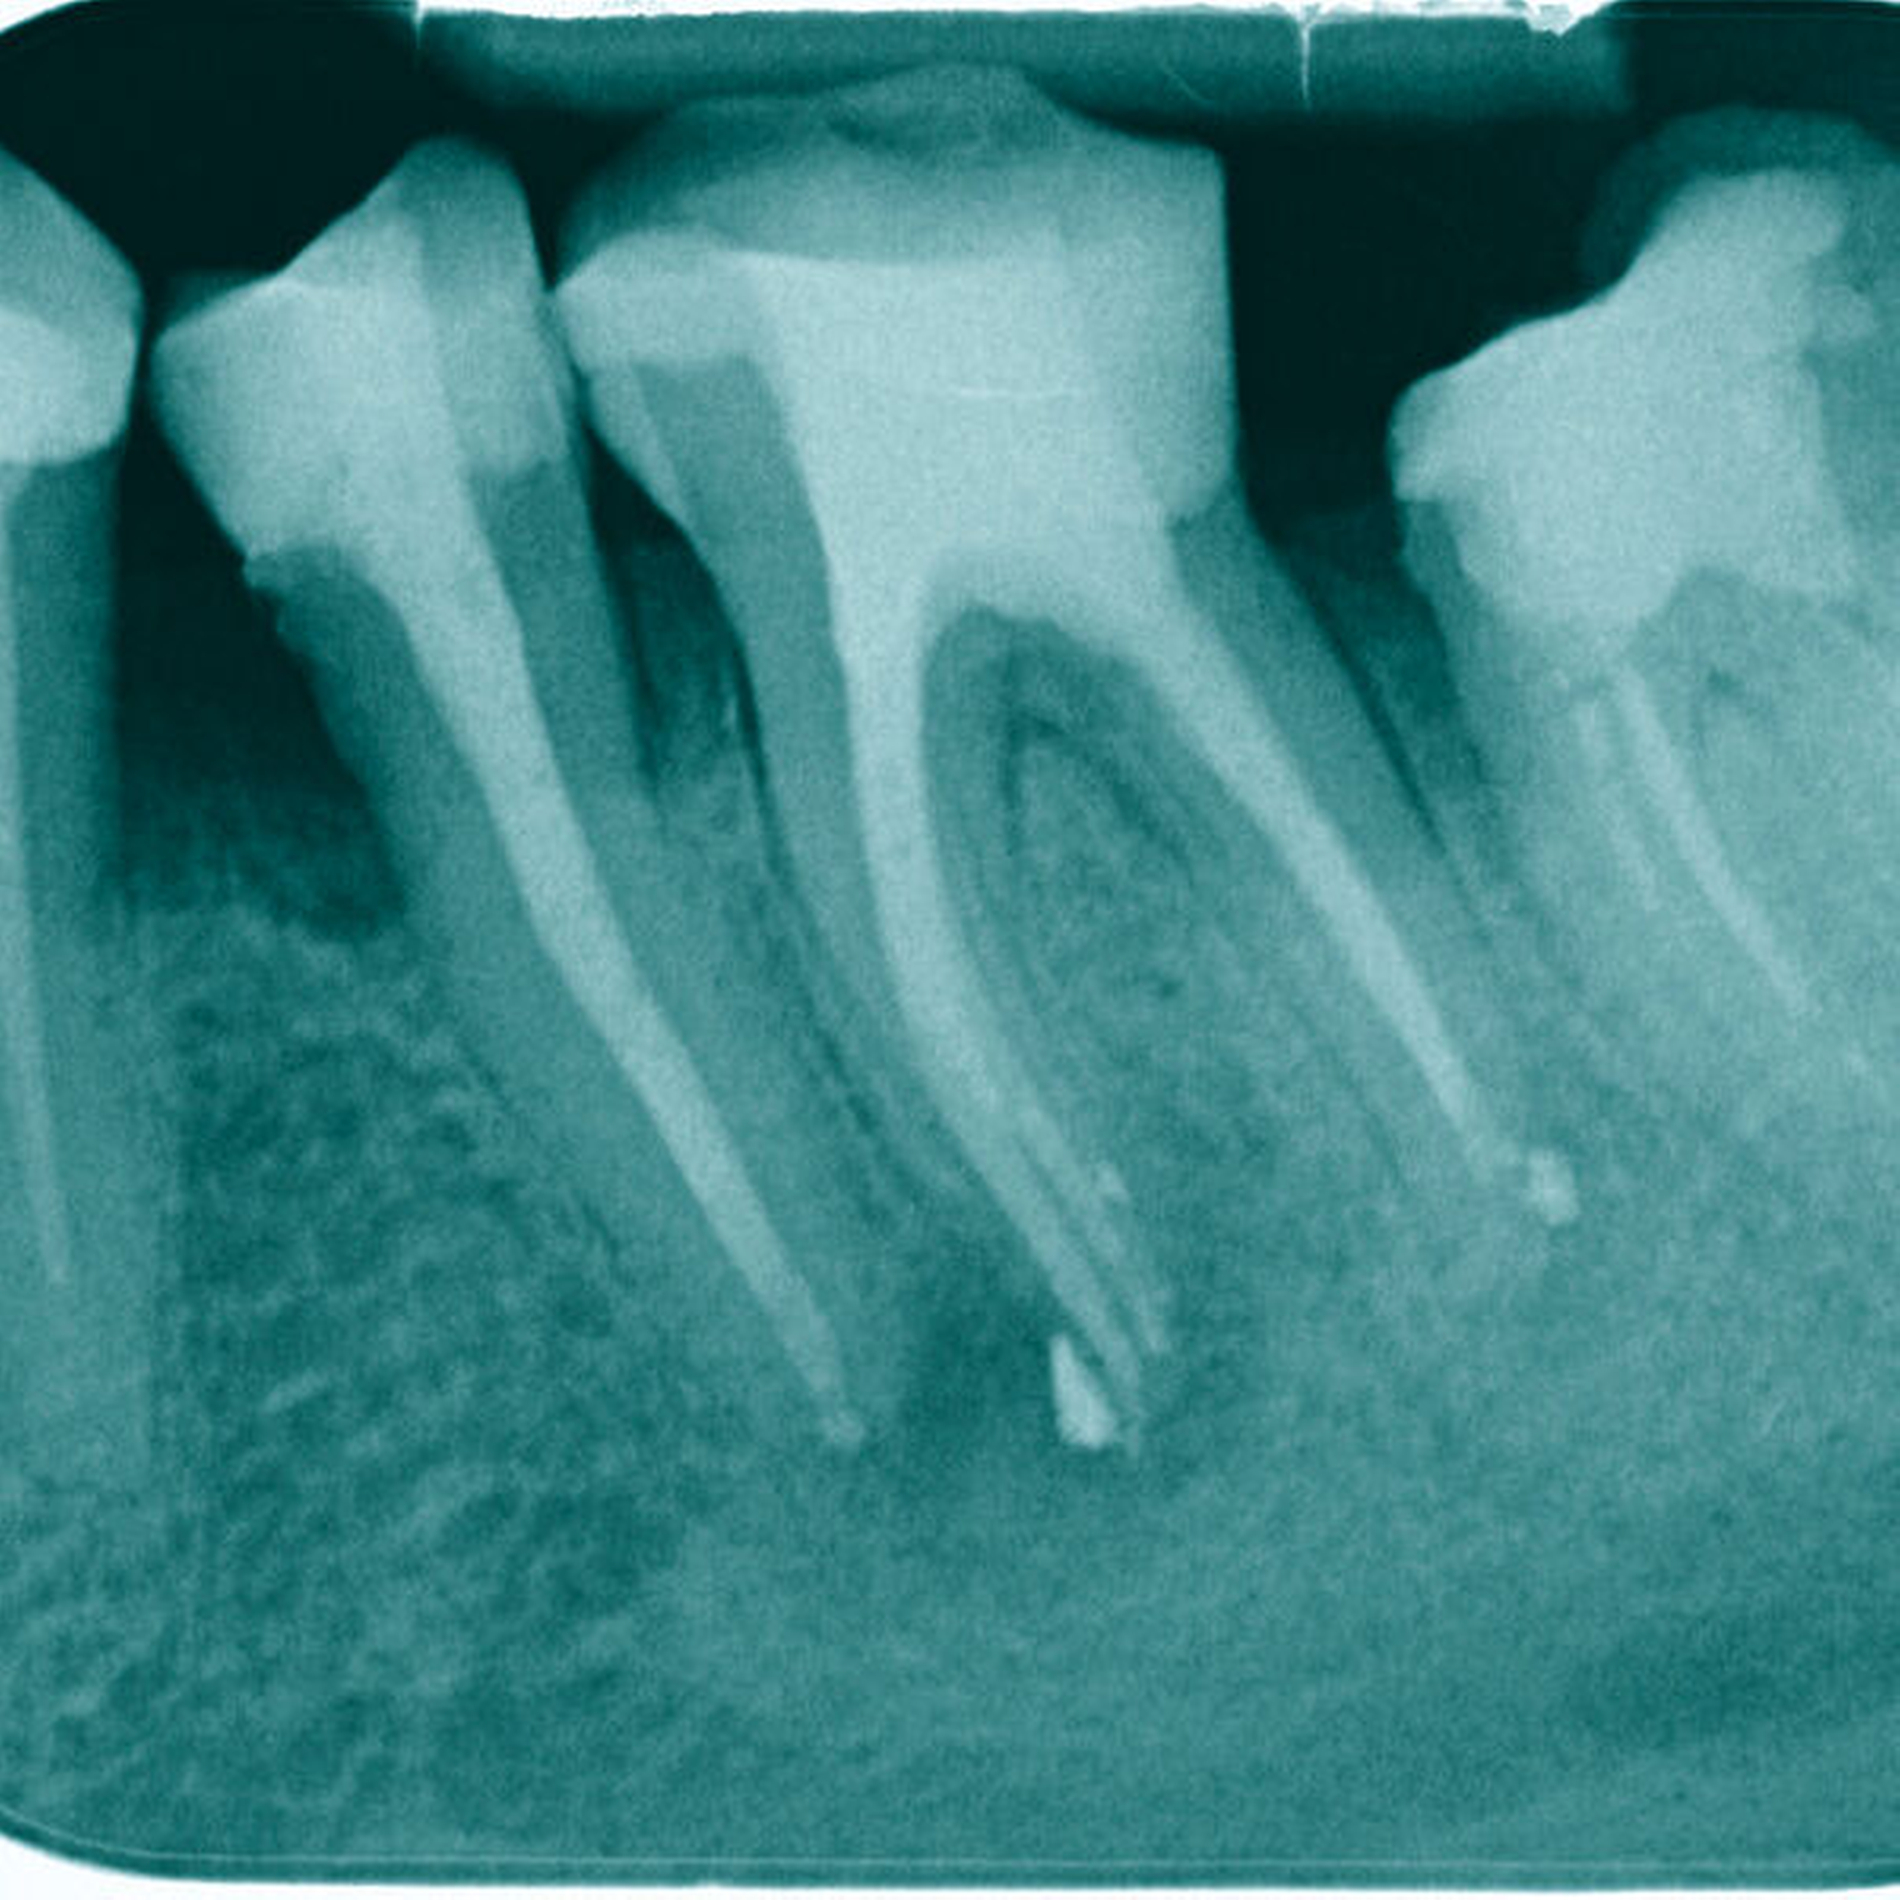

Auch in diesem Fall konnte in allen drei Wurzelkanälen Durchgängigkeit erreicht werden. Die chemomechanische Aufbereitung und Obturation (warm-vertikal modifiziert nach Schilder) der Wurzelkanäle erfolgte in zwei weiteren Sitzungen (Abbildung 9). Nach acht Monaten erfolgte der erste Recall, wobei eine deutliche Heilungstendenz erkennbar war (Abbildung 10).